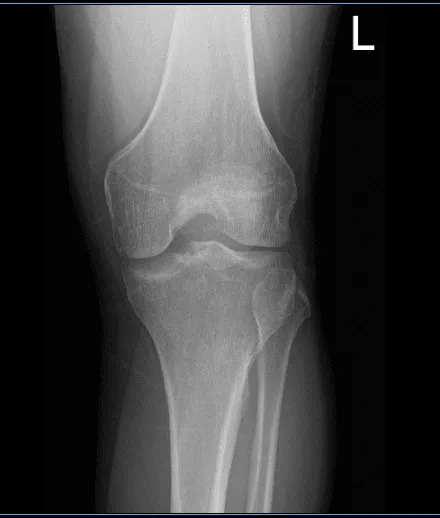

Patient is here with complaints of left knee pain. He is 26 year-old and currently employed as an electrician. He hurt his knee three months ago and is unsure exactly how, maybe he twisted it accidentally. He is not able to bend or extend the knee and is hopping with a limp and not able to bear weight on the foot. He is here with X-rays on his left knee.

X-ray results showed that there is mild lateral compartment joint space narrowing. We discussed treatment options on his condition including Physical Therapy, MRI, Injection and Surgery. We agreed to go with 3 tesla MRI left knee, he also agreed to start the PT and continue Rest/Ice/Compression/ Elevation Therapy.